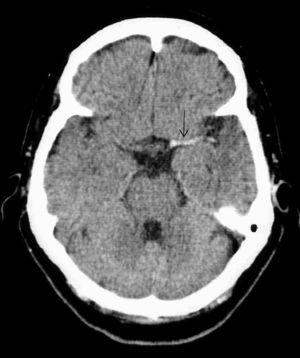

Paciente de 73 años con antecedentes de hipertensión arterial (HTA), diabetes no insulino-dependiente, hipotiroidismo, hipercolesterolemia y bronquitis crónica. Fue trasladada a nuestro hospital por el servicio de emergencias extrahospitalaria por un cuadro brusco de insuficiencia respiratoria y disminución del nivel de conciencia con hemiparesia derecha. A su ingreso en el hospital está intubada con Glasgow Coma Score (GCS) 6, presión arterial (PA): 240/100 mmHg, anisocoria con midriasis izquierda, hemiplejía derecha y Babinsky derecho. Se realiza tomografía axial computarizada (TAC) cerebral (fig. 1) que aprecia hiperdensidad de la arteria cerebral media derecha como signo precoz de lesión isquémica que todavía no se visualiza. Al ingreso en nuestra unidad se la mantiene sedada, en ventilación mecánica, controlando la PA y con tratamiento antiagregante. A las 48 horas se repite la TAC (fig. 2), observándose trombosis de la arteria cerebral media izquierda e hipodensidad frontotemporoparietal izquierda. Se mantiene consciente, afásica y hemipléjica pudiendo ser extubada y trasladada a planta. Posteriormente fallece por las secuelas de su enfermedad. El diagnóstico fue accidente cerebrovascular agudo (ACVA) isquémico y trombosis de la arteria cerebral media izquierda.

Figura 2